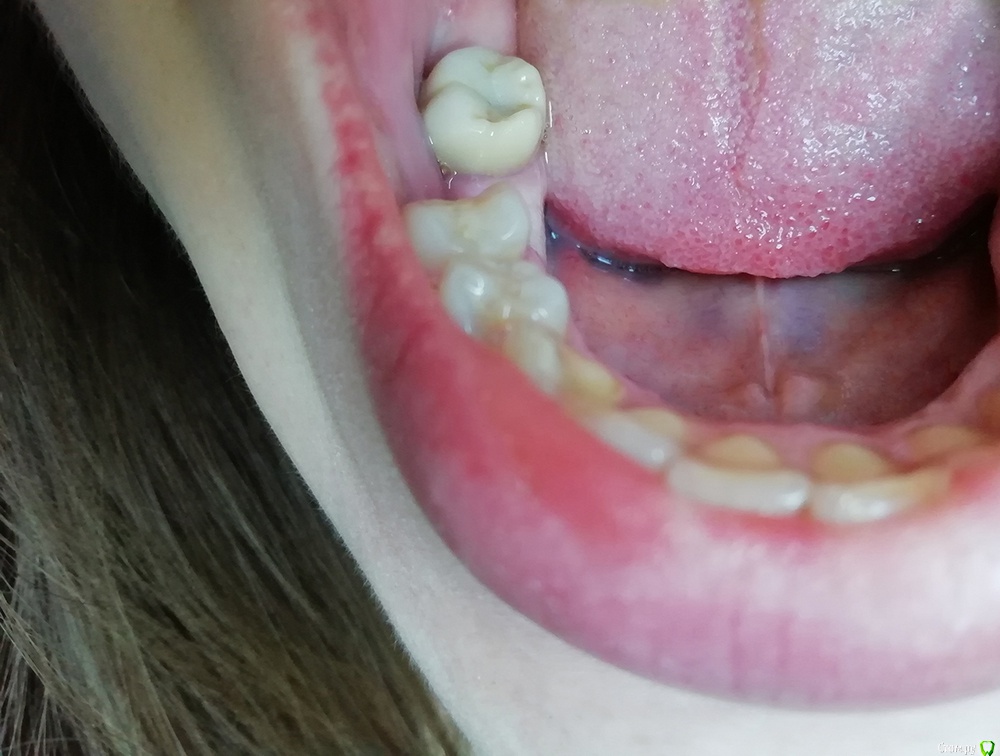

nataganka Опубликовано 16 апреля, 2019 Автор Поделиться Опубликовано 16 апреля, 2019 Выкладываю было-стало. Один зуб сделан полностью. Как и писала выше, вкладка разборная из золото-платинового сплава, коронка диоксид циркония без керамики, потом еще снимок выложу. Дальше буду лечить 24 зуб, все-таки там не камень, а кариес под десной. Затем буду делать все тоже самое с 36 зубом (вкладка из золота, коронка цирконий) и покажу результат 36-го. Вкладку ставлю у одного доктора, коронку у другого. Вопросов не возникло ни у одного из докторов, оба согласились так работать. Изначально планировала все делать у одного доктора рекомендованного мне здесь, но в их клинике не делают золотые вкладки. Еле-еле нашла где в Москве делают вкладки из золота и врач понравился А коронку уже ставлю у рекомендованного здесь на форуме в личке доктора, доктор тоже понравился. Ссылка на комментарий